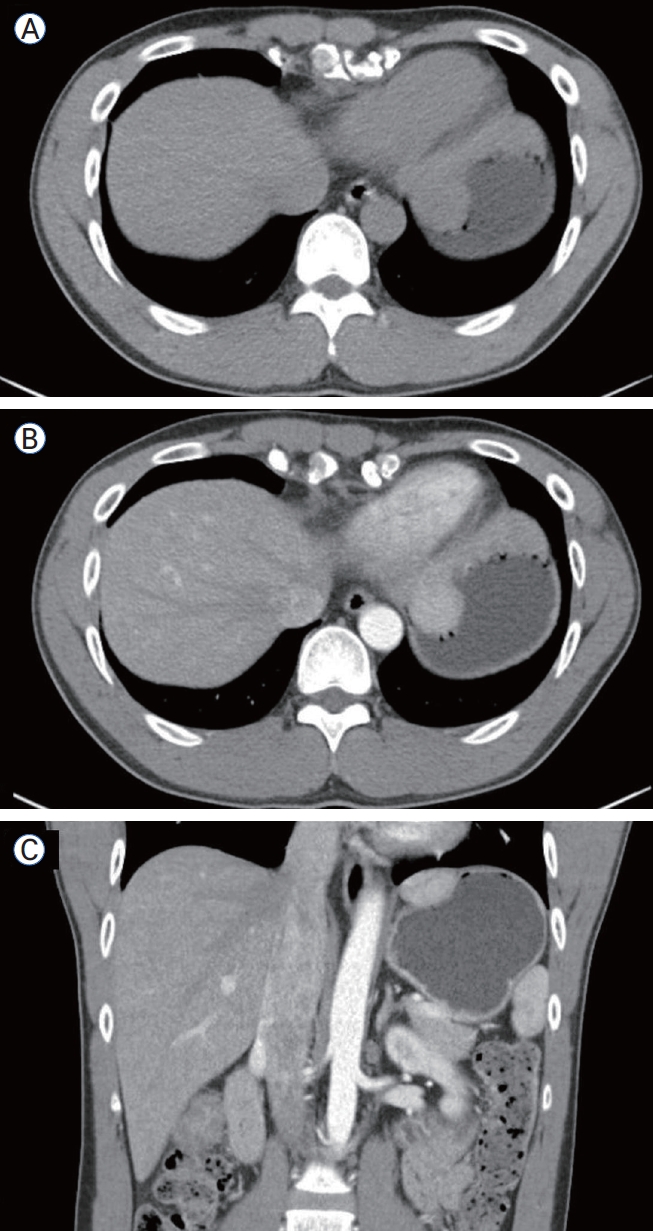

복부 조영증강 전산화단층촬영(computed tomography, CT)에서는 병변이 위 저부에 국한되어 조영증강되었고(Fig. 2) 인접한 간과의 해부학적 연속성이 관찰되지 않아 초기에는 위벽 기원 병변으로 추정되었다. 일반적으로 부속 간엽의 경우 stalk이 관찰되거나 간과의 연속성이 시사되나[2] 본 증례에서는 CT상 명확히 구별되지 않았다.

Figure 2.

Abdominal CT findings. Low-attenuation lesion at the gastric fundus on pre-contrast axial view (A), showing enhancement on contrast-enhanced axial and coronal views (B, C). CT, computed tomography.